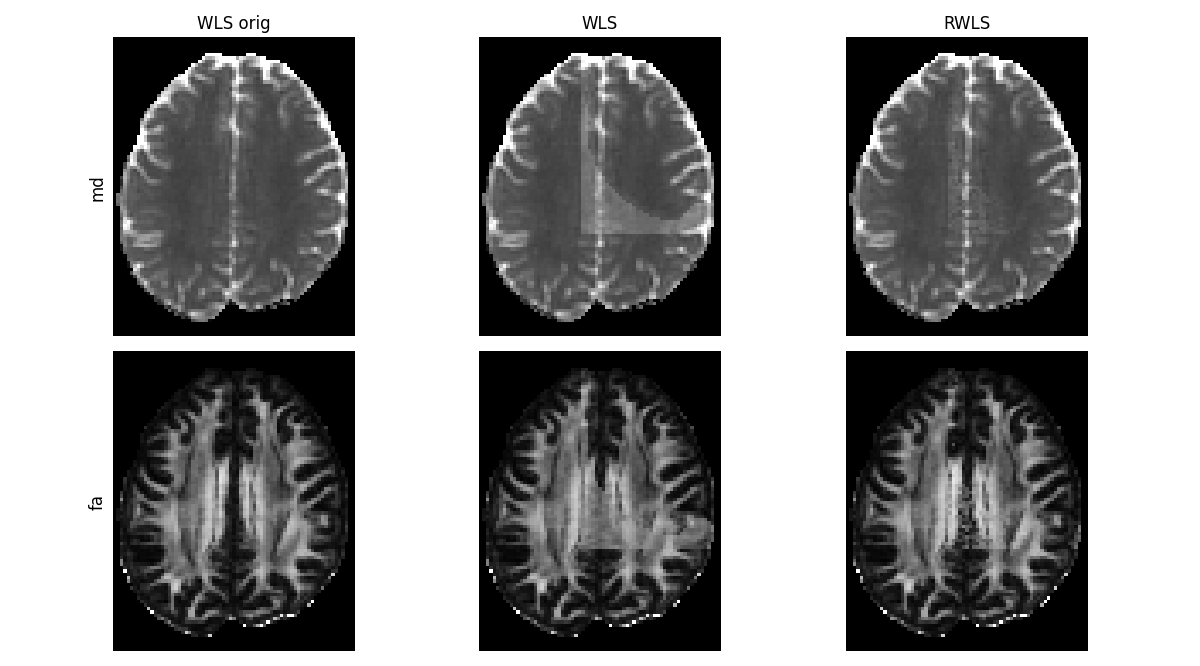

Here are MD and FA for the different fits:

compare_maps(

[tenfit_orig, tenfit, tenfit_rwls],

["md", "fa"],

fit_labels=["WLS orig", "WLS", "RWLS"],

map_kwargs=[{"vmin": 0.000, "vmax": 0.002}, {"vmin": 0, "vmax": 1.0}],

filename="Compare_WLS_and_RWLS.png",

)

WLS and RWLS on the corrupted data, compared to the original fit.